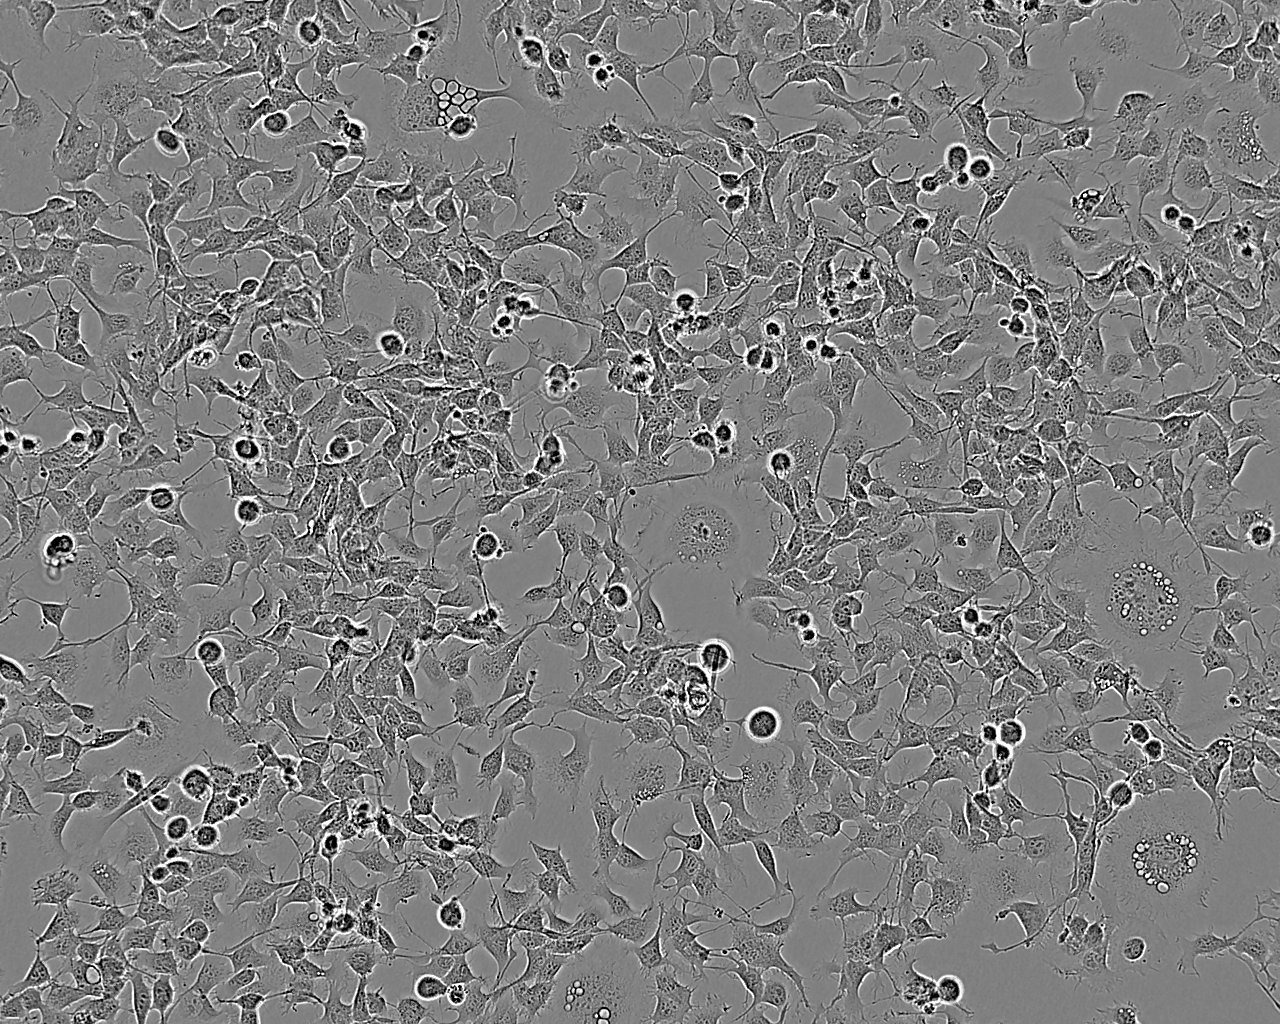

细胞背景资料:肝内胆管癌;男性

细胞形态:上皮细胞样

细胞生长:贴壁

细胞生长特性:贴壁